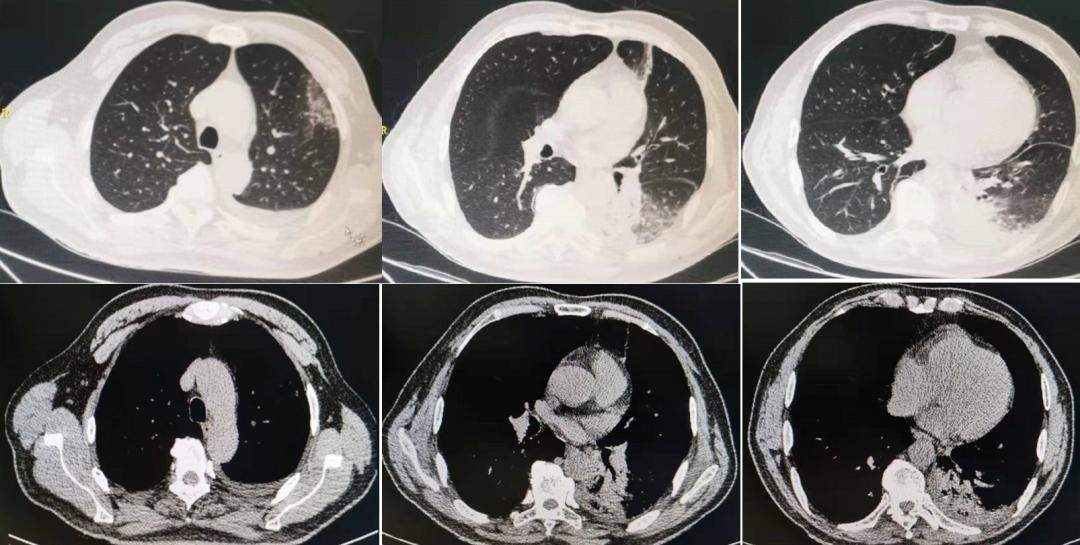

从排除中枢神经相关疾病,考虑周围神经病,再到怀疑肺部感染,进而得到验证,整个过程还算顺利,判断比较及时,未耽搁太多时间。既然「矛头」现已明确转向呼吸系统疾病,为了进一步明确患者的肺部病变,转入我科后立即对患者行胸部CT检查(图3)。

图3:胸部CT:双肺炎症,左侧为主,左侧胸腔少量积液,伴局部肺不张,心包少量积液。